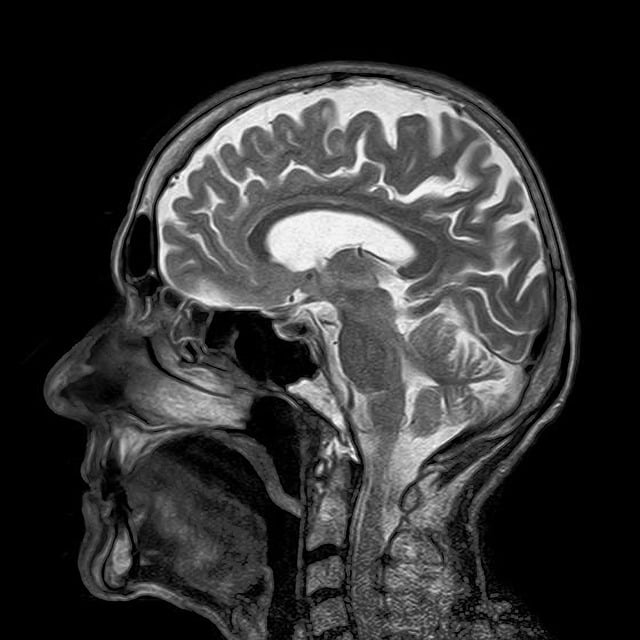

1-2 MRI(자기공명영상)

· 뇌의 구조와 혈류를 자세히 확인할 수 있습니다. MRI는 보다 정밀한 이미지를 제공하여 뇌의 손상 부위를 명확히 파악합니다.

· 예시- 뇌의 손상 지역을 정확히 파악하기 위해 MRI 촬영.